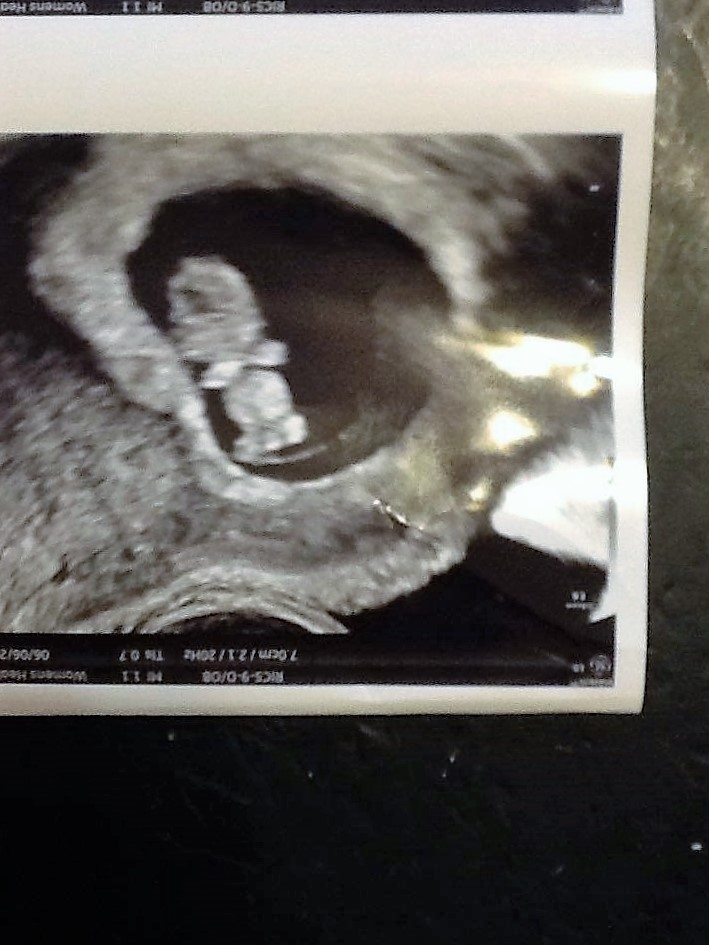

I'm new to this board. This is my third pregnancy in a little over 3 years. The first two pregnancies ended in MC (actually, the second was a still birth due to SCH). Hubby and I have been together for almost 10 years, and it took us almost 4 years to get pregnant the first time. The fact that it ended in MC, and then our son was born at 14 weeks, was just devastating. We actually kind of just stopped trying after that. We weren't necessarily trying to prevent, either. So in May I go to the ER because I think I'm passing a kidney stone and lo and behold, I'm pregnant! It was a shocker to say the least (almost 3 years exactly to the day our son was born). I was immediately terrified. I'm now 9w6d, and so far everything has went amazing. We just had our second ultrasound (technically 4th) at 9w1d, and we even got to see baby move a little. Up to that point Hubby and I (regretfully and defensively) had been a little resigned to feeling anything about this baby. BUT, once we saw it move and heard it's sweet little heart beat, we were both in love. Which scares me even more now, the heartbreak will be even greater. We go back July 5th (which seems FOREVER away) for our NT scan. We are due on January 9th. Here's a picture of our sweet little gummy bear.

I flipped the image to make it a little easier for my MIL to understand, and it got saved that way. LOL!